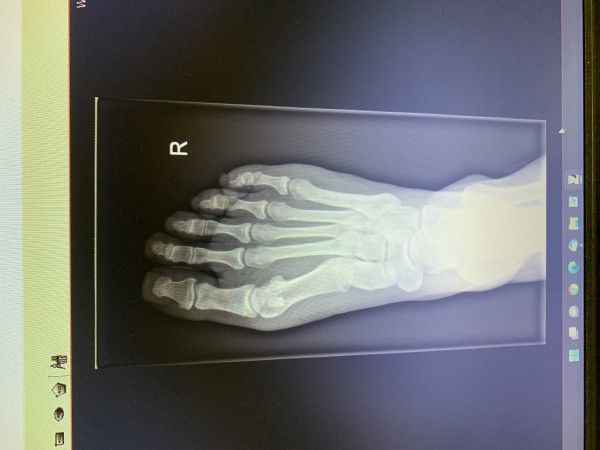

Witam, po weselu mam okropną opuchliznę w okolicy haluksa i dużego palca, ból ma charakter narywającego, w załączeniu zdjęcie. Co to może być?